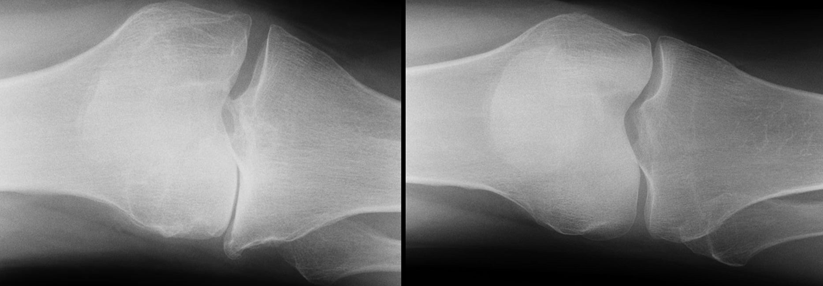

Röntgen:

• primäres Verfahren zum Nachweis einer Arthrose

• Arthroseanzeichen sind Gelankspaltverschmälerung, subchondrale Sklerosierung, Geröllzysten, Osteophyten

• in schweren Fällen Deformierung des Gelenkes, sekundäre Chondrokalzinose

• Funktionsaufnahmen z.B. des Knies zum Nachweis der Bandinstabilität